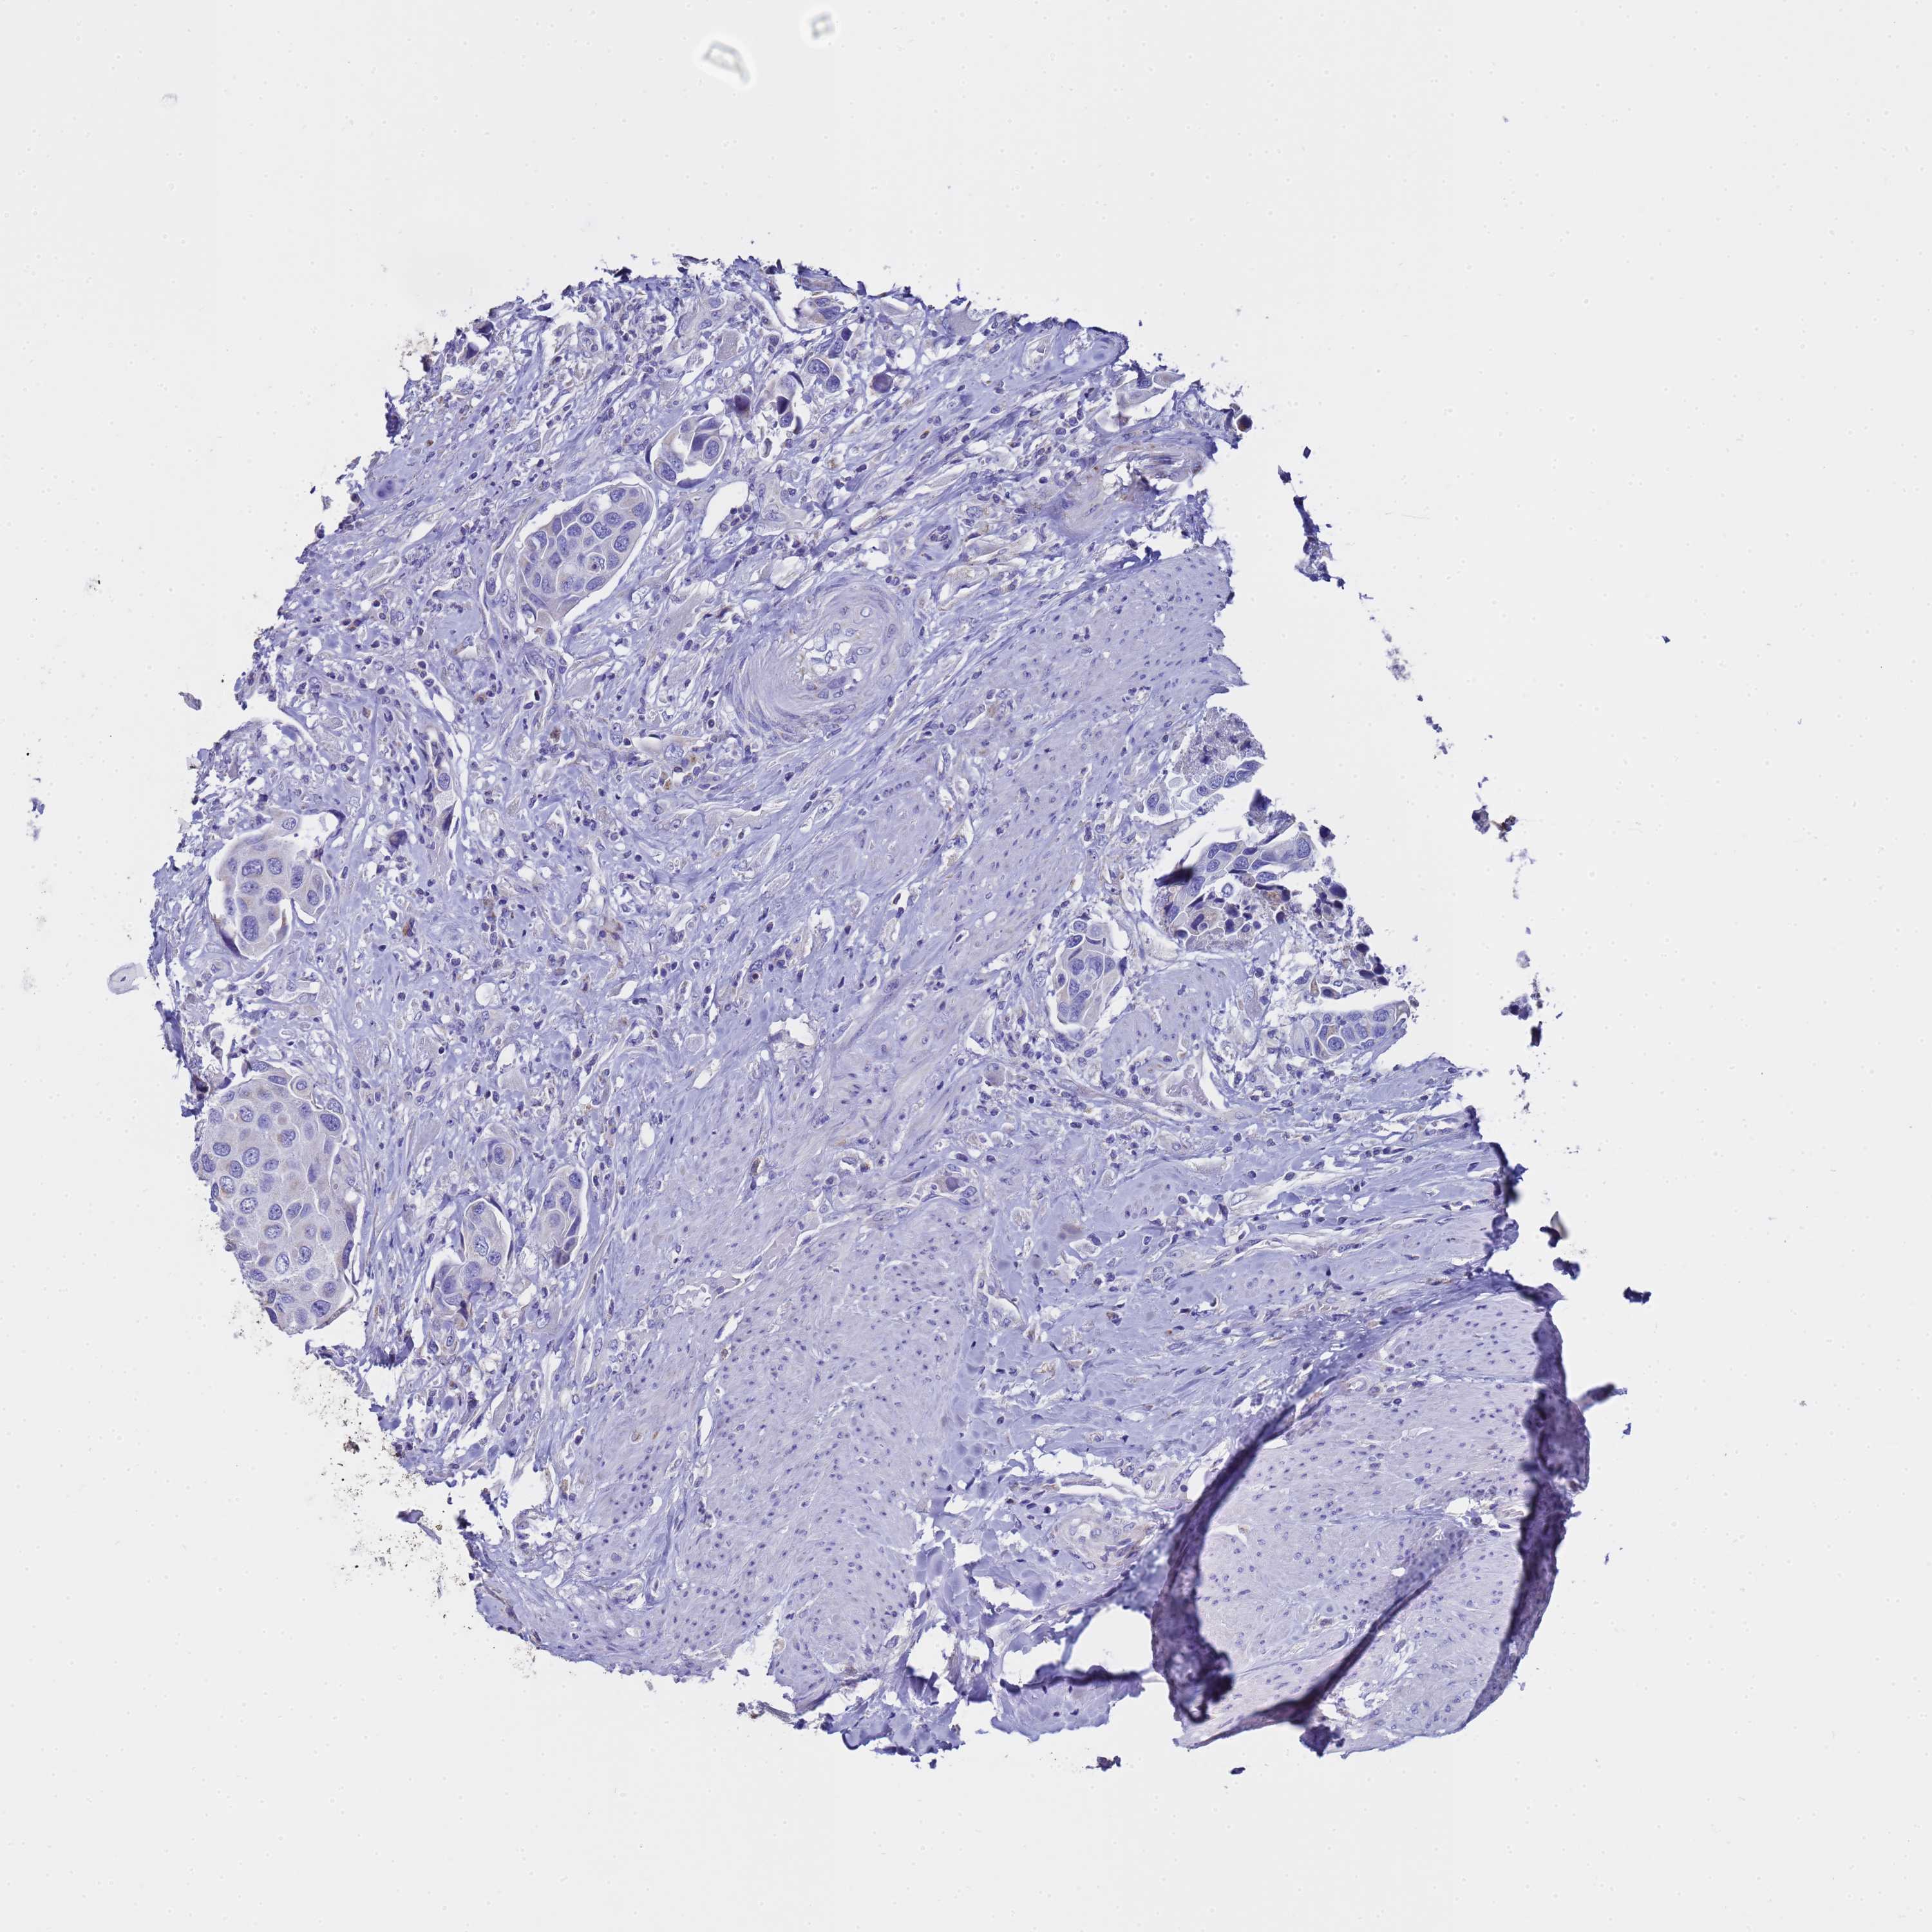

UROTHELIAL CANCER - Protein expressioni

A mouse-over function shows sample information and annotation data. Click on an image to view it in a full screen mode. Samples can be filtered based on level of antibody staining by selecting one or several of the following categories: high, medium, low and not detected. The assay and annotation is described here.

Note that samples used for immunohistochemistry by the Human Protein Atlas do not correspond to samples in the TCGA dataset.

Antibody stainingi

Antibody staining in the annotated cell types in the current human tissue is reported as not detected, low, medium, or high, based on conventional immunohistochemistry profiling in selected tissues. This score is based on the combination of the staining intensity and fraction of stained cells.

Each image is clickable and will lead to virtual microscopy that enables deeper exploration of all samples and also displays staining intensity scores, fraction scores and subcellular localization as well as patient and tissue information for each sample.

Antibody HPA046775

Antibody HPA050633

Urothelial carcinoma, High grade

Urothelial carcinoma, Low grade

Urothelial carcinoma, NOS